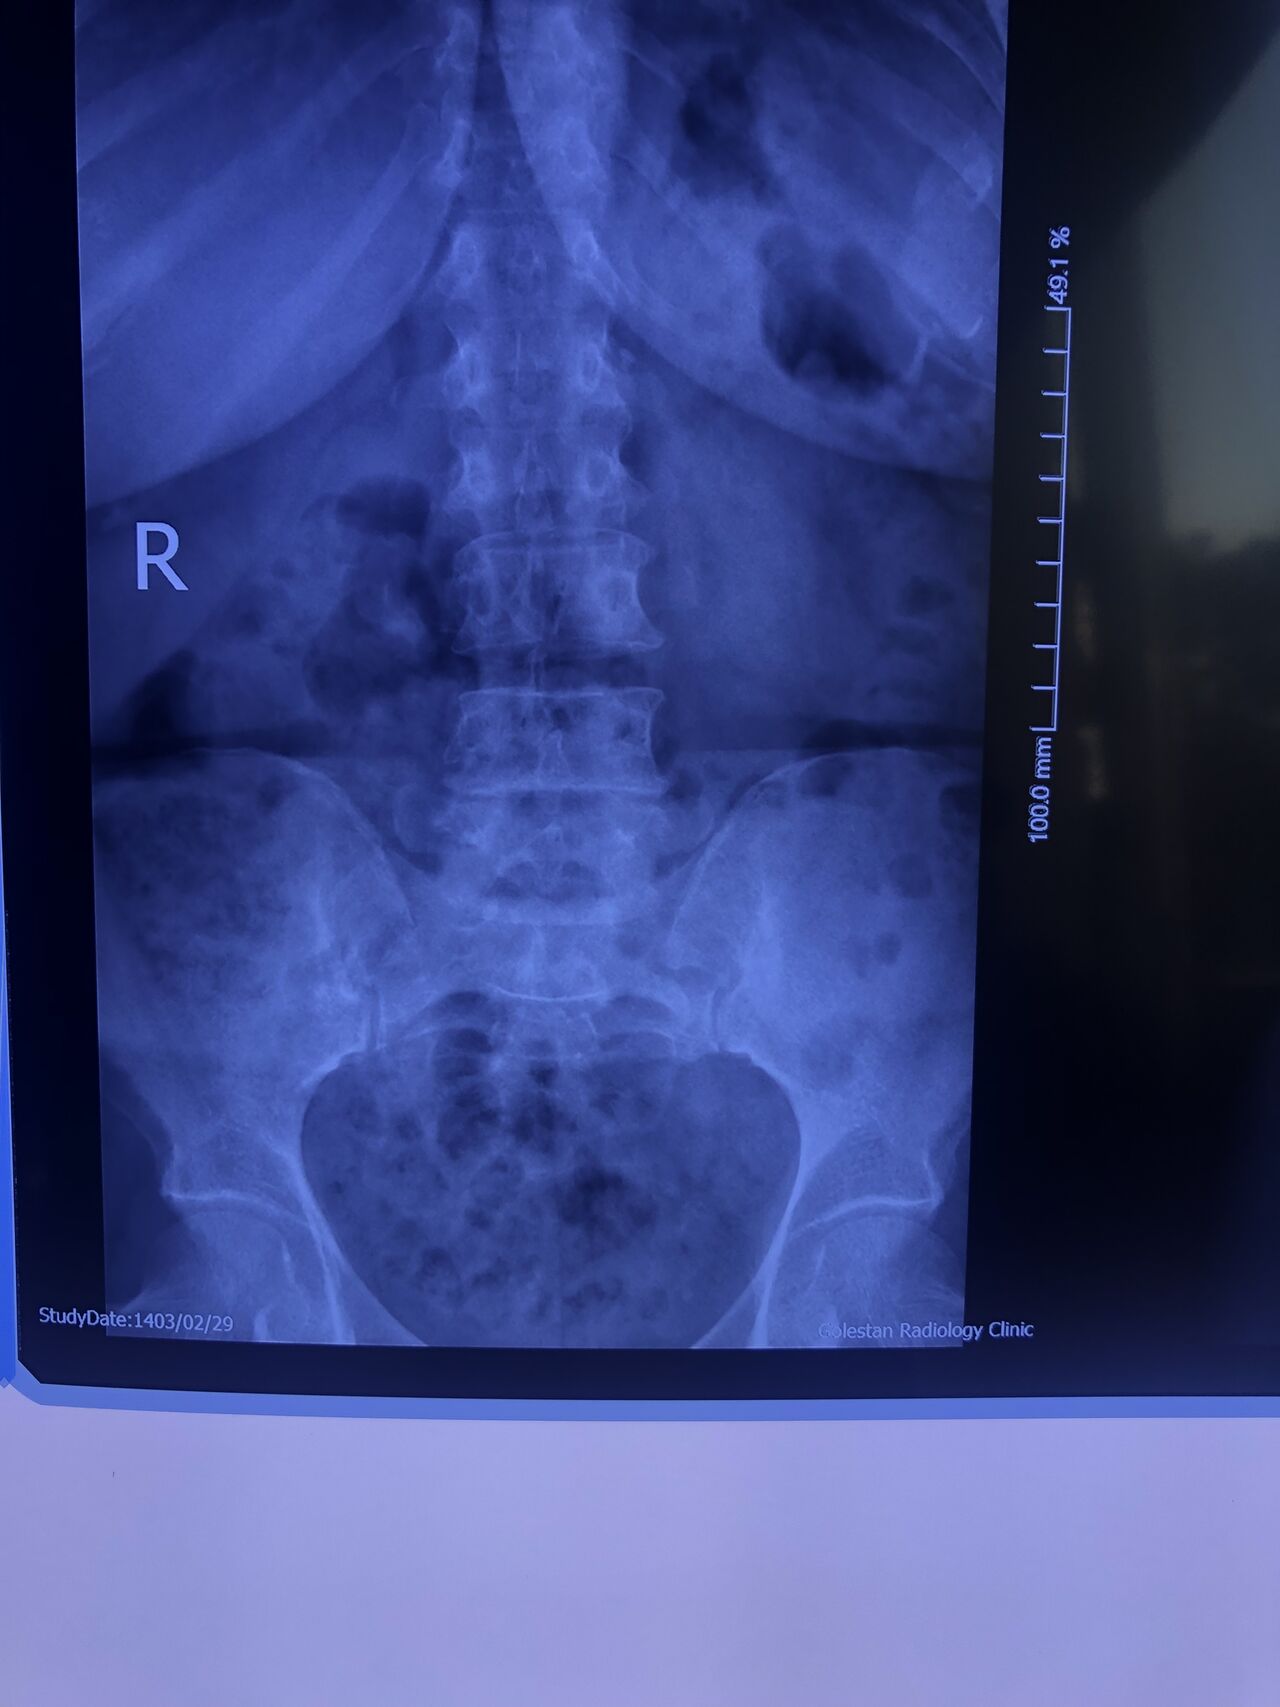

Case 15

70 yrs old female presented to my clinic today (Oct 06/2024)due to severe LBP with both legs pain for several years.

7 years ago came to my clinic with L leg radicular pain and I referred her to a neurosurgeon. Patient underwent full laminectomy from L1 to S1. Few months after surgery her LBP and legs pain were started and hasn’t improved since then. Now walking aggravates the pain and forces her to bend forward. Patient had mri from 6 months ago. Her mri 7 years ago was similar to the recent mri, just laminectomy and soft tissue collection has been added. In neurological examination p.tvdid not have any neurological deficits. I ordered lower limbs emg/ncv, dynamic lumbar spine X.ray. As a chiropractic Doctor what would be your plan of management for this patient?